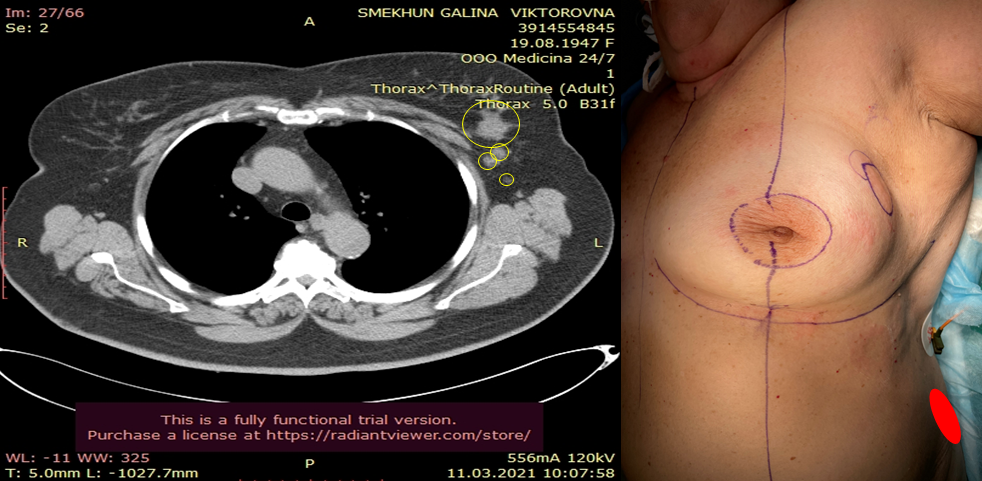

Пациентка Г.В. 74 года

Диагноз: люминальный B, HER2 отрицательный тип, рак левой молочной железы T2N0M0 G2.

Операция: радикальная секторальная резекция левой молочной железы